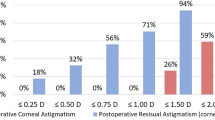

Surgical outcomes of toric intraocular lens (IOL) implantation for 8 years after surgery were analyzed. Data were retrospectively collected in 176 eyes of 176 patients before and 1 month, 1, 3, 5, and 8 years after phacoemulsification and implantation of a toric IOL. Preoperative corneal and postoperative manifest astigmatism was analyzed by converting to power vector notations; horizontal/vertical (J0) and oblique (J45) astigmatism components. Toric IOL implantation significantly reduced pre-existing astigmatism by decreasing J0 in eyes with preoperative with-the-rule (WTR) astigmatism, increasing J0 in eyes with against-the-rule (ATR) astigmatism, and correcting J45 in eyes with oblique astigmatism. After surgery, the eyes with preoperative ATR astigmatism showed a significant ATR astigmatic shift, and J0 at 5 and 8 years was significantly smaller than that at 1 month postoperatively. Uncorrected distance visual acuity was also significantly worse at 5 and 8 years than at 1 month postoperatively. In eyes with WTR and oblique astigmatism, the effects of toric IOLs on astigmatism and visual acuity were sustained for 8 years. The long-term astigmatism-correcting effects did not differ among the models of toric IOL used in this study, SN6AT3–8 (Alcon Laboratories). In eyes with preoperative ATR astigmatism, astigmatism-correcting effects of toric IOLs decreased at 5 years and later postoperatively, indicating that overcorrection may be considered at the time of cataract surgery. In eyes with WTR and oblique astigmatism, the effects of toric IOLs were maintained throughout the 8-year follow-up period.

The time course of changes in J0 and J45 are shown in Fig. 1. The mean J0 significantly decreased after surgery (p = 0.002), while mean J45 did not show significant changes (p = 0.902). All postoperative J0 values from 1 month to 8 years were significantly smaller than the preoperative J0 value (p < 0.001).

Time course of changes in astigmatism. Toric IOL implantation significantly decreased J0 (p = 0.002), but not J45 (p = 0.902). When postoperative values from 1 month to 8 years were compared, statistically significant changes were found in J0 (p < 0.001) but not in J45 (p = 0.743). The J0 at 5 years (*p = 0.008) and 8 years (**p < 0.001) were significantly smaller than J0 at 1 month postoperatively.

When postoperative values from 1 month to 8 years were compared, statistically significant changes were found in J0 (p < 0.001), but not in J45 (p = 0.743). The mean J0 at 5 years (p = 0.008) and 8 years (p < 0.001) postoperatively were significantly smaller than the mean J0 at 1 month postoperatively. From 1 month to 8 years after surgery, J0 declined by 0.201 ± 0.563 D. Double-angle plot analyses of preoperative corneal astigmatism and manifest astigmatism at 1 month and 8 years postoperatively are shown in Fig. 2.

Changes in J0 and J45 were analysed in eyes with preoperative WTR (Fig. 3), ATR (Fig. 4), and oblique astigmatism (Fig. 5). Toric IOL implantation significantly reduced preoperative astigmatism in all groups. In eyes with WTR astigmatism, surgery significantly decreased J0 (p < 0.001), but not J45 (p = 0.782). In eyes with ATR astigmatism, J0 significantly increased by surgery (p < 0.001), while no change was found in J45 (p = 0.825). In eyes with oblique astigmatism, surgery induced a significant increase in J45 (p = 0.045), but not in J0 (p = 0.912).

Time course of changes in astigmatism in eyes with preoperative against-the-rule astigmatism. Toric IOL implantation significantly increased J0 (p < 0.001), but not J45 (p = 0.825). When postoperative values were compared, J0 showed significant changes after surgery (p < 0.001), and J0 values at 5 years (*p < 0.001) and 8 years (*p < 0.001) were significantly smaller than that at 1 month postoperatively. The mean J45 remained stable from 1 month to 8 years after surgery (p = 0.964).

Time course of changes in astigmatism in eyes with preoperative oblique astigmatism. Toric IOL implantation significantly increased J45 (p = 0.045), but not J45 (p = 0.912). When postoperative values were compared, J0 (p = 0.972) and J45 (p = 0.189) did not change significantly from 1 month to 8 years.

When postoperative values from 1 month to 8 years were compared, there were no significant fluctuations in J0 (p = 0.511) and J45 (p = 0.679) in eyes with WTR astigmatism (Fig. 3). In eyes with ATR astigmatism (Fig. 4), J0 value showed significant changes after surgery (p < 0.001), and J0 at 5 years (p < 0.001) and 8 years (p < 0.001) postoperatively were significantly smaller than that at 1 month postoperatively. The mean J45 remained steady after surgery (p = 0.964). In eyes with oblique astigmatism (Fig. 5), J0 (p = 0.972) and J45 (p = 0.189) did not fluctuate significantly from 1 month to 8 years after surgery.

We found that toric IOL implantation significantly reduced pre-existing astigmatism regardless of the type of preoperative corneal astigmatism; by decreasing power vector notation J0 (horizontal/vertical astigmatism component) in eyes with WTR astigmatism, increasing J0 in eyes with ATR astigmatism, and correcting J45 (oblique astigmatism component) in eyes with oblique astigmatism. Long-term astigmatism-correcting effects of toric IOLs, however, varied depending on the type of preoperative astigmatism. In eyes with WTR and oblique astigmatism, postoperative astigmatism remained stable from 1 month to 8 years after surgery. On the other hand, in eyes with ATR astigmatism, there was a constant decline in postoperative J0, and mean J0 at 5 years and later was significantly smaller than that at 1 month postoperatively, indicating a significant ATR astigmatic shift after surgery. From 1 month to 8 years postoperatively, J0 was reduced by 0.201 ± 0.563 D. This result is in good agreement with a previous study by Hayashi et al.27 who reported ATR astigmatic changes of 0.33 D over 10 years after 4.1-mm incision sutureless cataract surgery in patients who were 61.8 ± 6.0 years old at baseline. They also reported that eyes that did not have surgery showed ATR changes of 0.21 D over 10 years from baseline age of 59.9 ± 5.8 years old. Gudmundsdottir et al.28 reported a mean ATR astigmatic change of 0.13 D over 5 years in a normal adult population who were 50 years and older at baseline. Judging from the results of these previous and current studies, long-term changes in astigmatism after small incision cataract surgery appear to represent the physiological ATR astigmatic shift that is commonly associated with aging.

In eyes with preoperative WTR and oblique astigmatism, postoperative changes in power vector notation J0 and J45 were not significant, indicating that astigmatism-correcting effects of toric IOLs in those eyes were maintained at least for 8 years after surgery. Hayashi et al.24 assessed long-term changes in the refractive effect of toric IOL implantation and reported similar results. In eyes with preoperative ATR astigmatism, manifest refractive and corneal astigmatism significantly changed toward ATR astigmatism during the 6.6-year follow-up period24. In eyes with preoperative WTR astigmatism, manifest refractive and corneal astigmatism did not change significantly for 6.8 years after surgery. Eyes with oblique astigmatism were not included in their study. Longer-term outcomes of toric IOL implantation, however, such as ≥ 10 years remain unknown. In fact, the J0 curve in Fig. 3 and J45 curve in Fig. 5 in the current study imply that astigmatism-correcting effects of toric IOLs may eventually wane if more extensive studies in terms of both length of the follow-up period and number of subjects are conducted. This would be the subject of future studies.

In conclusion, long-term surgical outcomes of cataract surgery with toric IOL implantation were investigated. Preoperative corneal and postoperative manifest astigmatism was converted to power vector notations J0 (horizontal/vertical component) and J45 (oblique component). In eyes with preoperative WTR and oblique astigmatism, the astigmatism-correcting effects continued during the 8-year follow-up period. In eyes with preoperative ATR astigmatism, postoperative astigmatism showed an ATR shift, and J0 at 5 and 8 years postoperatively was significantly lower than that at 1 month postoperatively. Visual acuity, especially UDVA, at 5 and 8 years after surgery was significantly worse than that at 1 month after surgery. Given these long-term trends, surgeons may consider overcorrection of astigmatism in eyes with preoperative ATR astigmatism at the time of cataract surgery using toric IOLs.